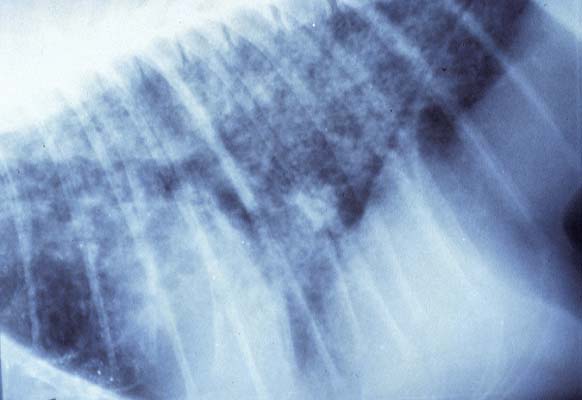

- Case 23-3. The A/P thoracic radiograph shows marked

right sided deviation of the cardiac silouette. The lateral thoracic

radiograph shows diffuse fluid density in dorsal lung fields.

- Thoracic radiographs demonstrated an increased pulmonary

interstitial pattern with air bronchograms bilaterally. The cardiac

silhouette was shifted to the right. Abdominal radiographs demonstrated